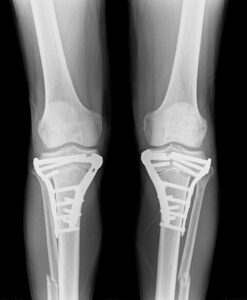

先日、左の人工股関節と左の人工膝関節手術を受けた70代の女性が、

転倒により左大腿骨骨折が生じたため手術治療を行いました。

人工股関節と人工膝関節の間で螺旋状に骨折しています。

通常であれば、膝関節を開けて逆行性髄内釘挿入手術を行います。

本来はそれほど難易度が高い手術ではありませんが、刺入部に膝人工関節、

固定すべき大腿骨近位に人工股関節があるため、挿入方向や髄内釘のサイズが限られ、

骨折整復が困難となります。

さらに、人工関節周囲に残存している骨が破綻した場合、

収集がつかない事態になるので、繊細な操作が要求されます。

強固な固定が得られたので、激痛のため身じろぎもできなかった状態から、

手術翌日には車椅子に移乗できるようになりました。